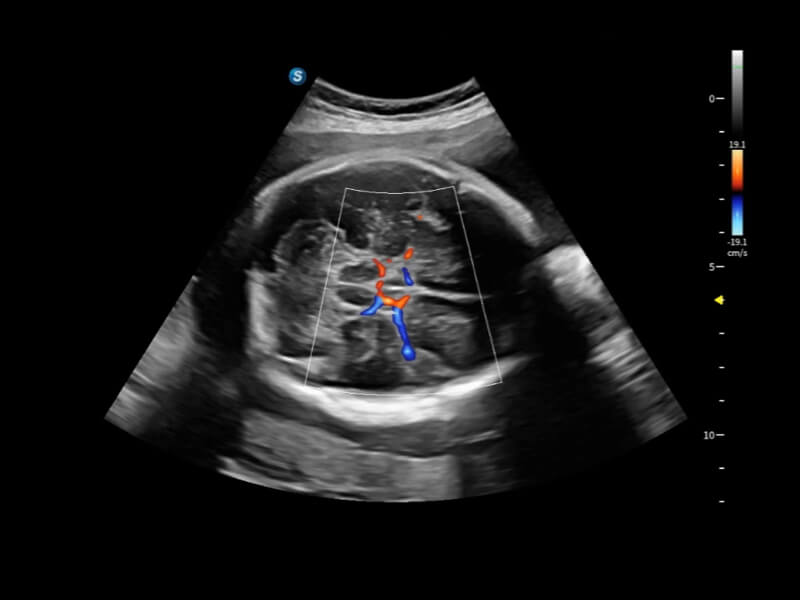

丰富的血流动力学检测技术,可在不同医疗场景中高效捕捉血流信号,助力临床诊疗。

在传统血流的基础上优化扫查和算法策略,能够更好的抑制组织信息,提炼红细胞运动信息,得到更高帧频,高灵敏度和分辨率的血流信号,还原更真实的血流动力学。